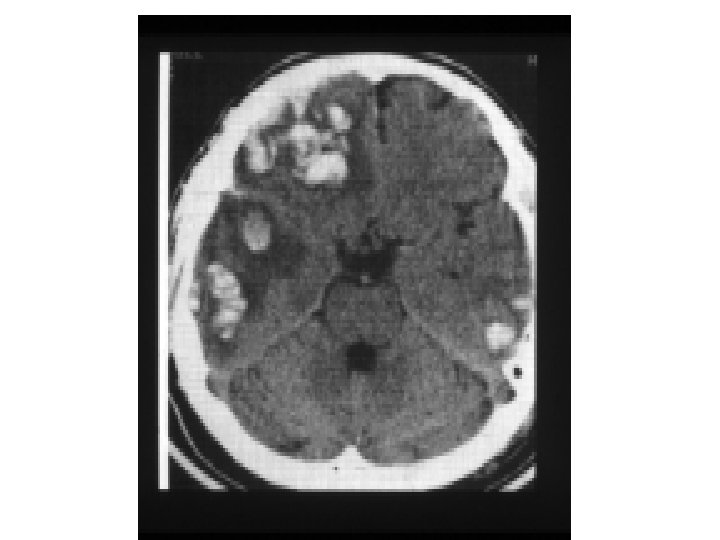

Sınıflandırma Morfolojik yapıya göre Kranial Fraktürler: Konveksite: - Linear/ parçalı - Deprese /nondeprese - Açık/kapalı Kafa tabanı: - Likör fistülü var /yok - Yedinci sinir hasarı var/ yok İntrakranial lezyonlar: Fokal: - Epidural - Subdural - İntraserebral Yaygın: - Konküzyon - Diffüz aksonal hasar

Subdural Hematom (SDH) • • Travma sonrası parenkim laserasyonu Yüzeyel veya asıcı venlerin kopması BT’de konkav görüntü Başvuru sırasında nörolojik tablo EDH’a göre daha kötü • Mortalite çok daha yüksek % 50 -60’lara kadar çıkabilir

Sekonder Beyin Hasarı • Sekonder beyin hasarının intrakranial nedenleri: - KİBAS - Geç intraserebral hematom - Beyin ödemi - Hiperemi - Epileptik nöbet - Vazospazm